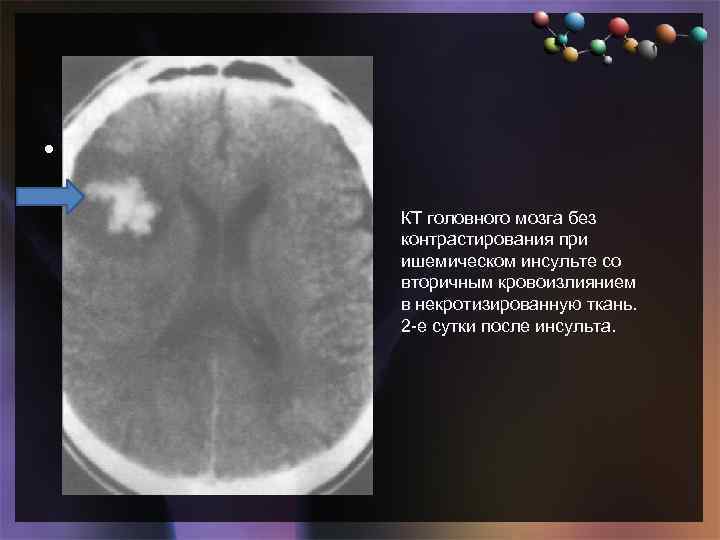

Иллюстрации и пояснения: гиподенсивный очаг на КТ головного мозга